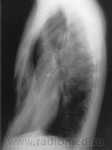

Извините за боковой.

Срединная тень смещена влево. Грудная клетка бочкообразной формы.

2. По боковой рентгенограмме, вот кажется мне, что имеем мы дело с воронкообразной грудной клеткой, что видно при осмотре "ад окулус".

Для определения степени деформации применяется индекс Гижицкой - это частное от деления наименьшего расстояния между задней поверхностью грудины и передней поверхностью тел позвонков на наибольшее. Эти расстояния измеряются по боковым проекциям рентгенограмм грудной клетки.